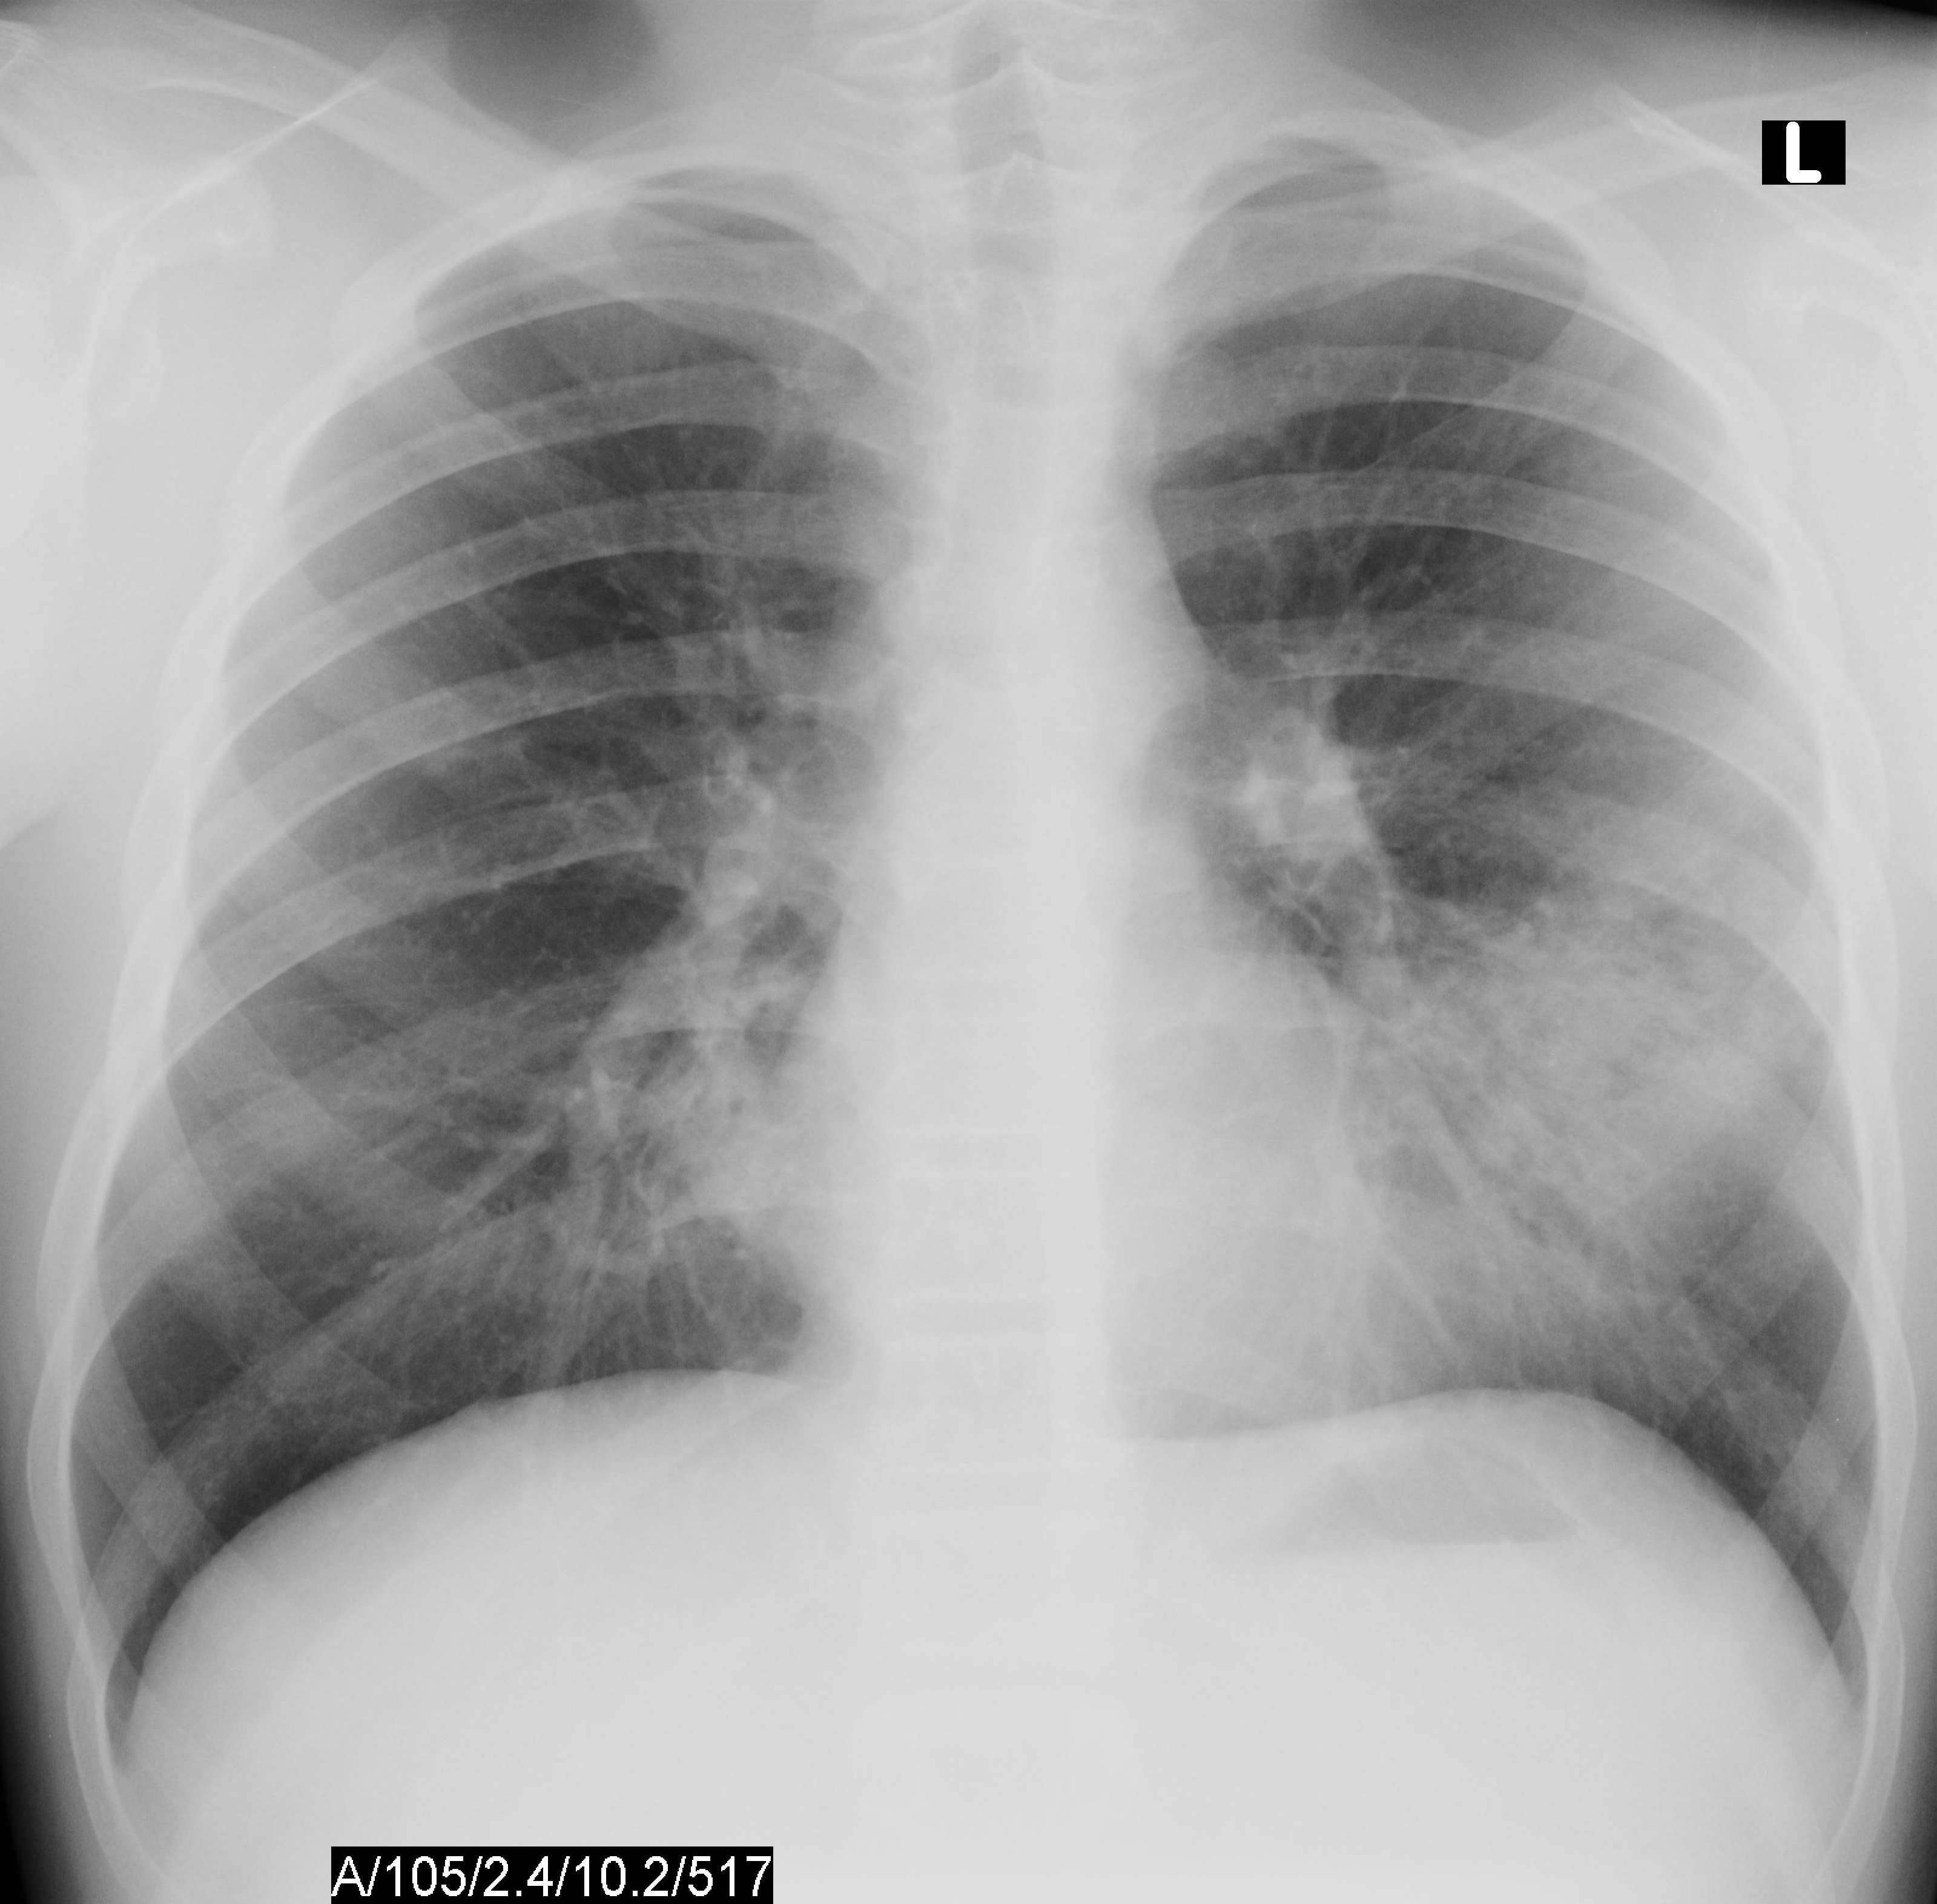

For this type of pneumonia performing a chest x-ray on the. Chest x-rays can reveal areas of opacity seen as white which represent consolidation. In complicated cases of pneumonia perform chest radiography 6 weeks after treatment to verify resolution of the pneumonia and to screen for any underlying predisposing.

This chest X-ray shows an area of lung inflammation indicating the presence of pneumonia. However chest X-ray examinations for pneumonia detection are prone to subjective variability 2 3. Please see disclaimer on my website.

It determines the pathogen that could have caused pneumonia. The differential for the radiologic finding of pulmonary consolidation includes blood pulmonary hemorrhage pus infection ie. We investigate whether chest radiographic findings could be used as predictors of severity of childhood pneumonia.

The Radiological Diagnosis Of Pneumonia In Children Pneumonia Full Text

The Radiological Diagnosis Of Pneumonia In Children Pneumonia Full Text